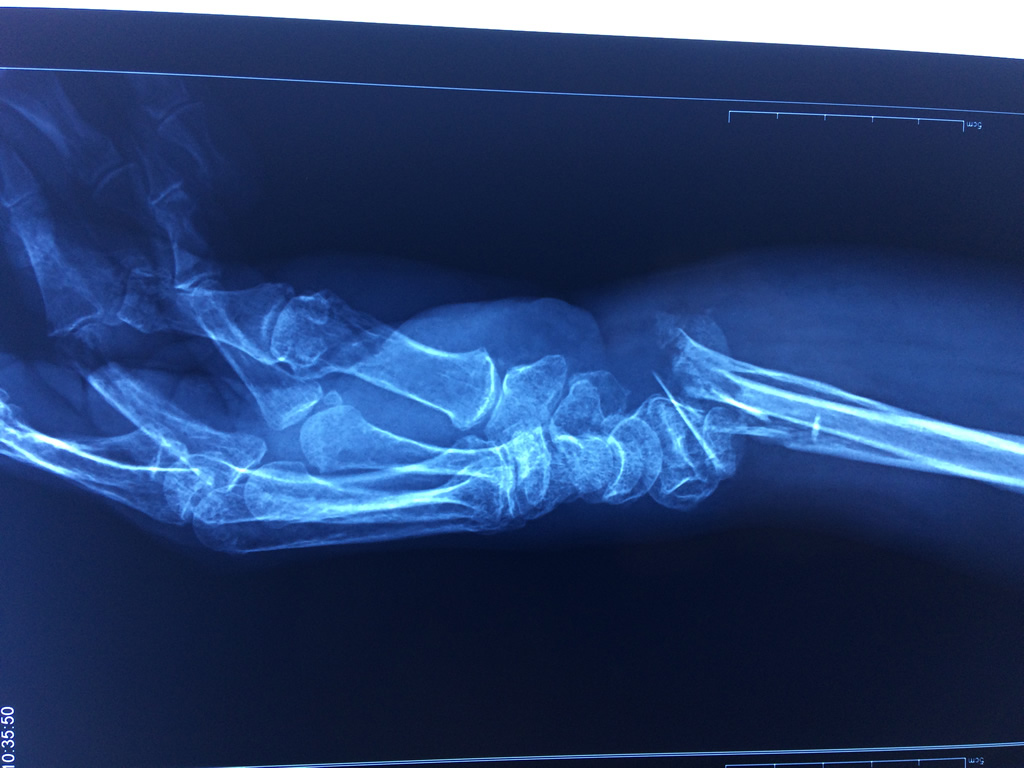

Cirugias en El Salvador - Cirugías de Muñecas y Manos

Los procedimientos más comunes en cirugía de la mano son aquellos destinados a reparar traumatismos, incluyendo lesiones de tendones, nervios, vasos sanguíneos, y articulaciones; huesos fracturados; y quemaduras, cortes, y otros daños de la piel.